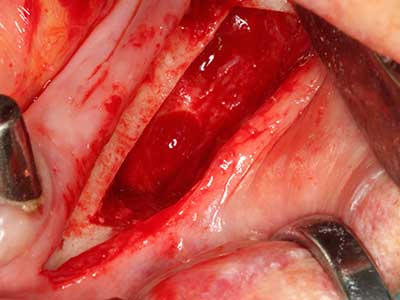

Quando le procedure chirurgiche vengono eseguite sull'osso nelle immediate vicinanze di strutture sensibili, come vasi sanguigni o nervi, gli strumenti rotanti pongono un rischio significativo di lesione iatrogena. I dispositivi piezoelettrici possono essere utili per la preparazione delle coperture ossee e la rimozione del tessuto duro in prossimità dei nervi, in particolare per la loro esposizione dopo una lesione iatrogena, ma anche durante la lateralizzazione dei nervi per le procedure di resezione e ricostruzione o il posizionamento di impianti (figg. 17-20). Il contatto leggero tra puntina piezoelettrica e nervo non causa generalmente danni, ma se si procede senza prestare attenzione con movimenti a sega o raccordi con residui di substrati ossei possono verificarsi danni al nervo temporanei o anche permanenti. Il rischio di danno, tuttavia, è considerato sostanzialmente inferiore al rischio presente utilizzando seghe o frese (Pereira, Gealh et al. 2014).

Indicazione: terapia parodontale